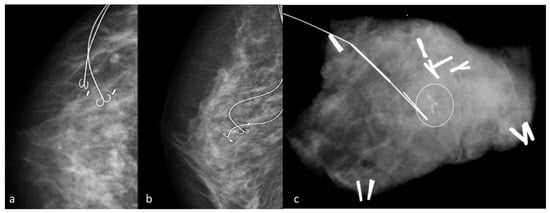

2. Wire Guided Localization

- Liberman, L.; Kaplan, J.; Van Zee, K.J.; Morris, E.A.; LaTrenta, L.R.; Abramson, A.F.; Dershaw, D.D. Bracketing wires for preoperative breast needle localization. Am. J. Roentgenol. 2001, 177, 565–572. [Google Scholar] [CrossRef] [PubMed]